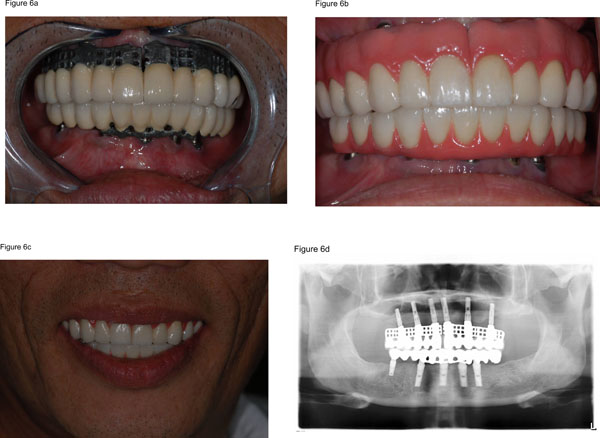

Rebuilding or replacing every tooth in the upper and lower jaws is part of whole mouth rehabilitation, sometimes referred to as full mouth restoration. The use of dental implants in this process has revolutionized the way dentists approach extensive tooth loss or damage. Implants serve as artificial tooth roots made of biocompatible materials like titanium, which integrate with the jawbone, providing a stable and permanent foundation for replacement teeth such as crowns, bridges, or dentures. This procedure does more than just improve appearance; it restores chewing ability, speech, and overall oral health.2. Who Should Consider Full Mouth Rehabilitation?

A complete smile makeover is a methodical procedure that calls for meticulous preparation and competent dental knowledge.• Consultation and Examination: Your dentist will conduct a thorough oral examination, including X-rays and 3D imaging, to assess bone health and plan treatment.

•Implant Placement: The implants are surgically inserted into the jawbone, usually under local anesthesia.

• Healing Phase: It takes several months for the implants to fuse with the bone, a process called osseointegration.

•Attachment of Prosthetics: After healing, custom-made crowns, bridges, or dentures are fixed onto the implants.